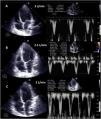

The increase in afterload conditioned by ECMO, together with low left ventricular contractility, can adversely affect aortic valve opening, with early closure of the valve (Supplementary material 13), or the valve may even remain closed (Fig. 3 and Supplementary material 14).

Lastly, many patients with VA ECMO may also carry some other left ventricular assist device (IAoBC, Impella®),33 and its position and function must be monitored as well.12 In the case of IAoBC, we can use TTE/TEE to observe insufflation of the balloon at the level of the descending aorta, with its distal extremity at the left subclavian root level (Supplementary material 17). Impella® can be explored with both TTE (long-axis parasternal or three-chamber apical) and TEE (mid-esophageal 120º), and we should see the device entering from the ascending aorta and the inlet or suction zone at 3–4 cm from the aortic valve34,35 (Fig. 4 and Supplementary material 18).

Weaning involves a progressive decrease (500 ml every 15–20 min) in VA ECMO support, gradually restoring cardiac preload. This requires adequate patient anticoagulation. We evaluate the hemodynamic (central venous pressure, mean and differential blood pressure, SvO2, SatO2) and echocardiographic repercussions of the procedure (LVEF, VTI, E wave, E’ wave or S’ of the lateral mitral ring) to a level (normally 1–1.5 l per min) indicating that the patient can tolerate suspension of the assist measures. During the latter, we check that LVEF is maintained or even exceeds 25%–30%, with VTI above 10 cm and an S’ wave of >6 cm/s (Fig. 5 and Supplementary material 22). In addition, we should also evaluate the behavior of the right-side cavities (TAPSE > 16 cm/S’ wave > 10 cm/s and RV size) and the possible appearance of signs of PHT (increase in peak velocity of tricuspid insufficiency (TI)) predicting RV failure.37–39

Echocardiographic evaluation of weaning in a patient with VA ECMO. Transthoracic echocardiography (TTE) and velocity-time integral (VTI) of the left ventricle outlet tract (LVOT) on reducing flow (A: 3 l/min, B: 2.5 l/min, C: 2 l/min) of VA ECMO. Note the increase in magnitude of VTI and consequently of stroke volume (SV) and cardiac output (CO).